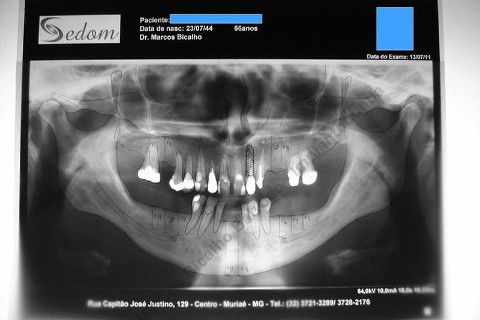

Paciente 66 anos, sexo feminino, procurou meus serviços para instalação de implante e coroa sobre implante na região do dente 22 com fratura radicular. Existem indicações para mais implantes mas a paciente está inrteressada no momento pela resolução deste caso.

Inicalmente estava planejado um implante cone morse 3.5 X 15,0 EX, mas resolvi experimentar um implante HI oferecido pelo vendedor da Bionnovation, como brinde (ele soube que estou preferindo o cone morse mas não trabalham com este sistema), e não consegui carga imediata neste implante. O travamento não foi satisfatório, ficou com um pouco mais de 20 N, menos de 25 N. Apesar desta ocorrência isto não significa que dará problema, apenas não fiz com carga imediata, aguardaremos 4 meses para a osseointegração.

Se o implante utilizado fosse o CM EX 3.5 X 15,0, além deste tipo de implante possuir característica autorosqueante, promovendo pelo seu design um melhor travamento, o seu comprimento de 15mm + 2mm infraósseo, conseguiríamos 6 mm de travamento em osso "virgem" (comprimento da raiz era de 11 mm) e travaria na cortical nasal. Mas este que usei, hexágono interno cônico, fica ao nível do rebordo; o maior que fabricam (comprimento de 15 mm), não apoiou em osso cortical e não é autorosqueante como o EX da Neodent.